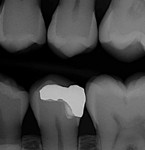

In the experience of the author, the rapid insertion along with the non-slumping, non-sticky sculptability of SonicFill makes placement time and effort rapid and easy, and similar to amalgam. This is something dentists have asked for since composite resins were first used for posterior restorations. In the case shown in Figure 1 through Figure 4, there is demonstrated adaptation to cavity walls without the need for a low-viscosity liner, which means this restoration was both clinically successful and more efficient to place. Figure 5 and Figure 6 show a case in which bulk-fill materials demonstrate both clinical success and longevity.